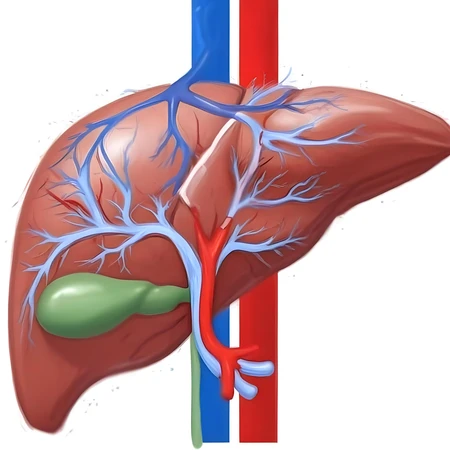

digital painting liver

34 Photos